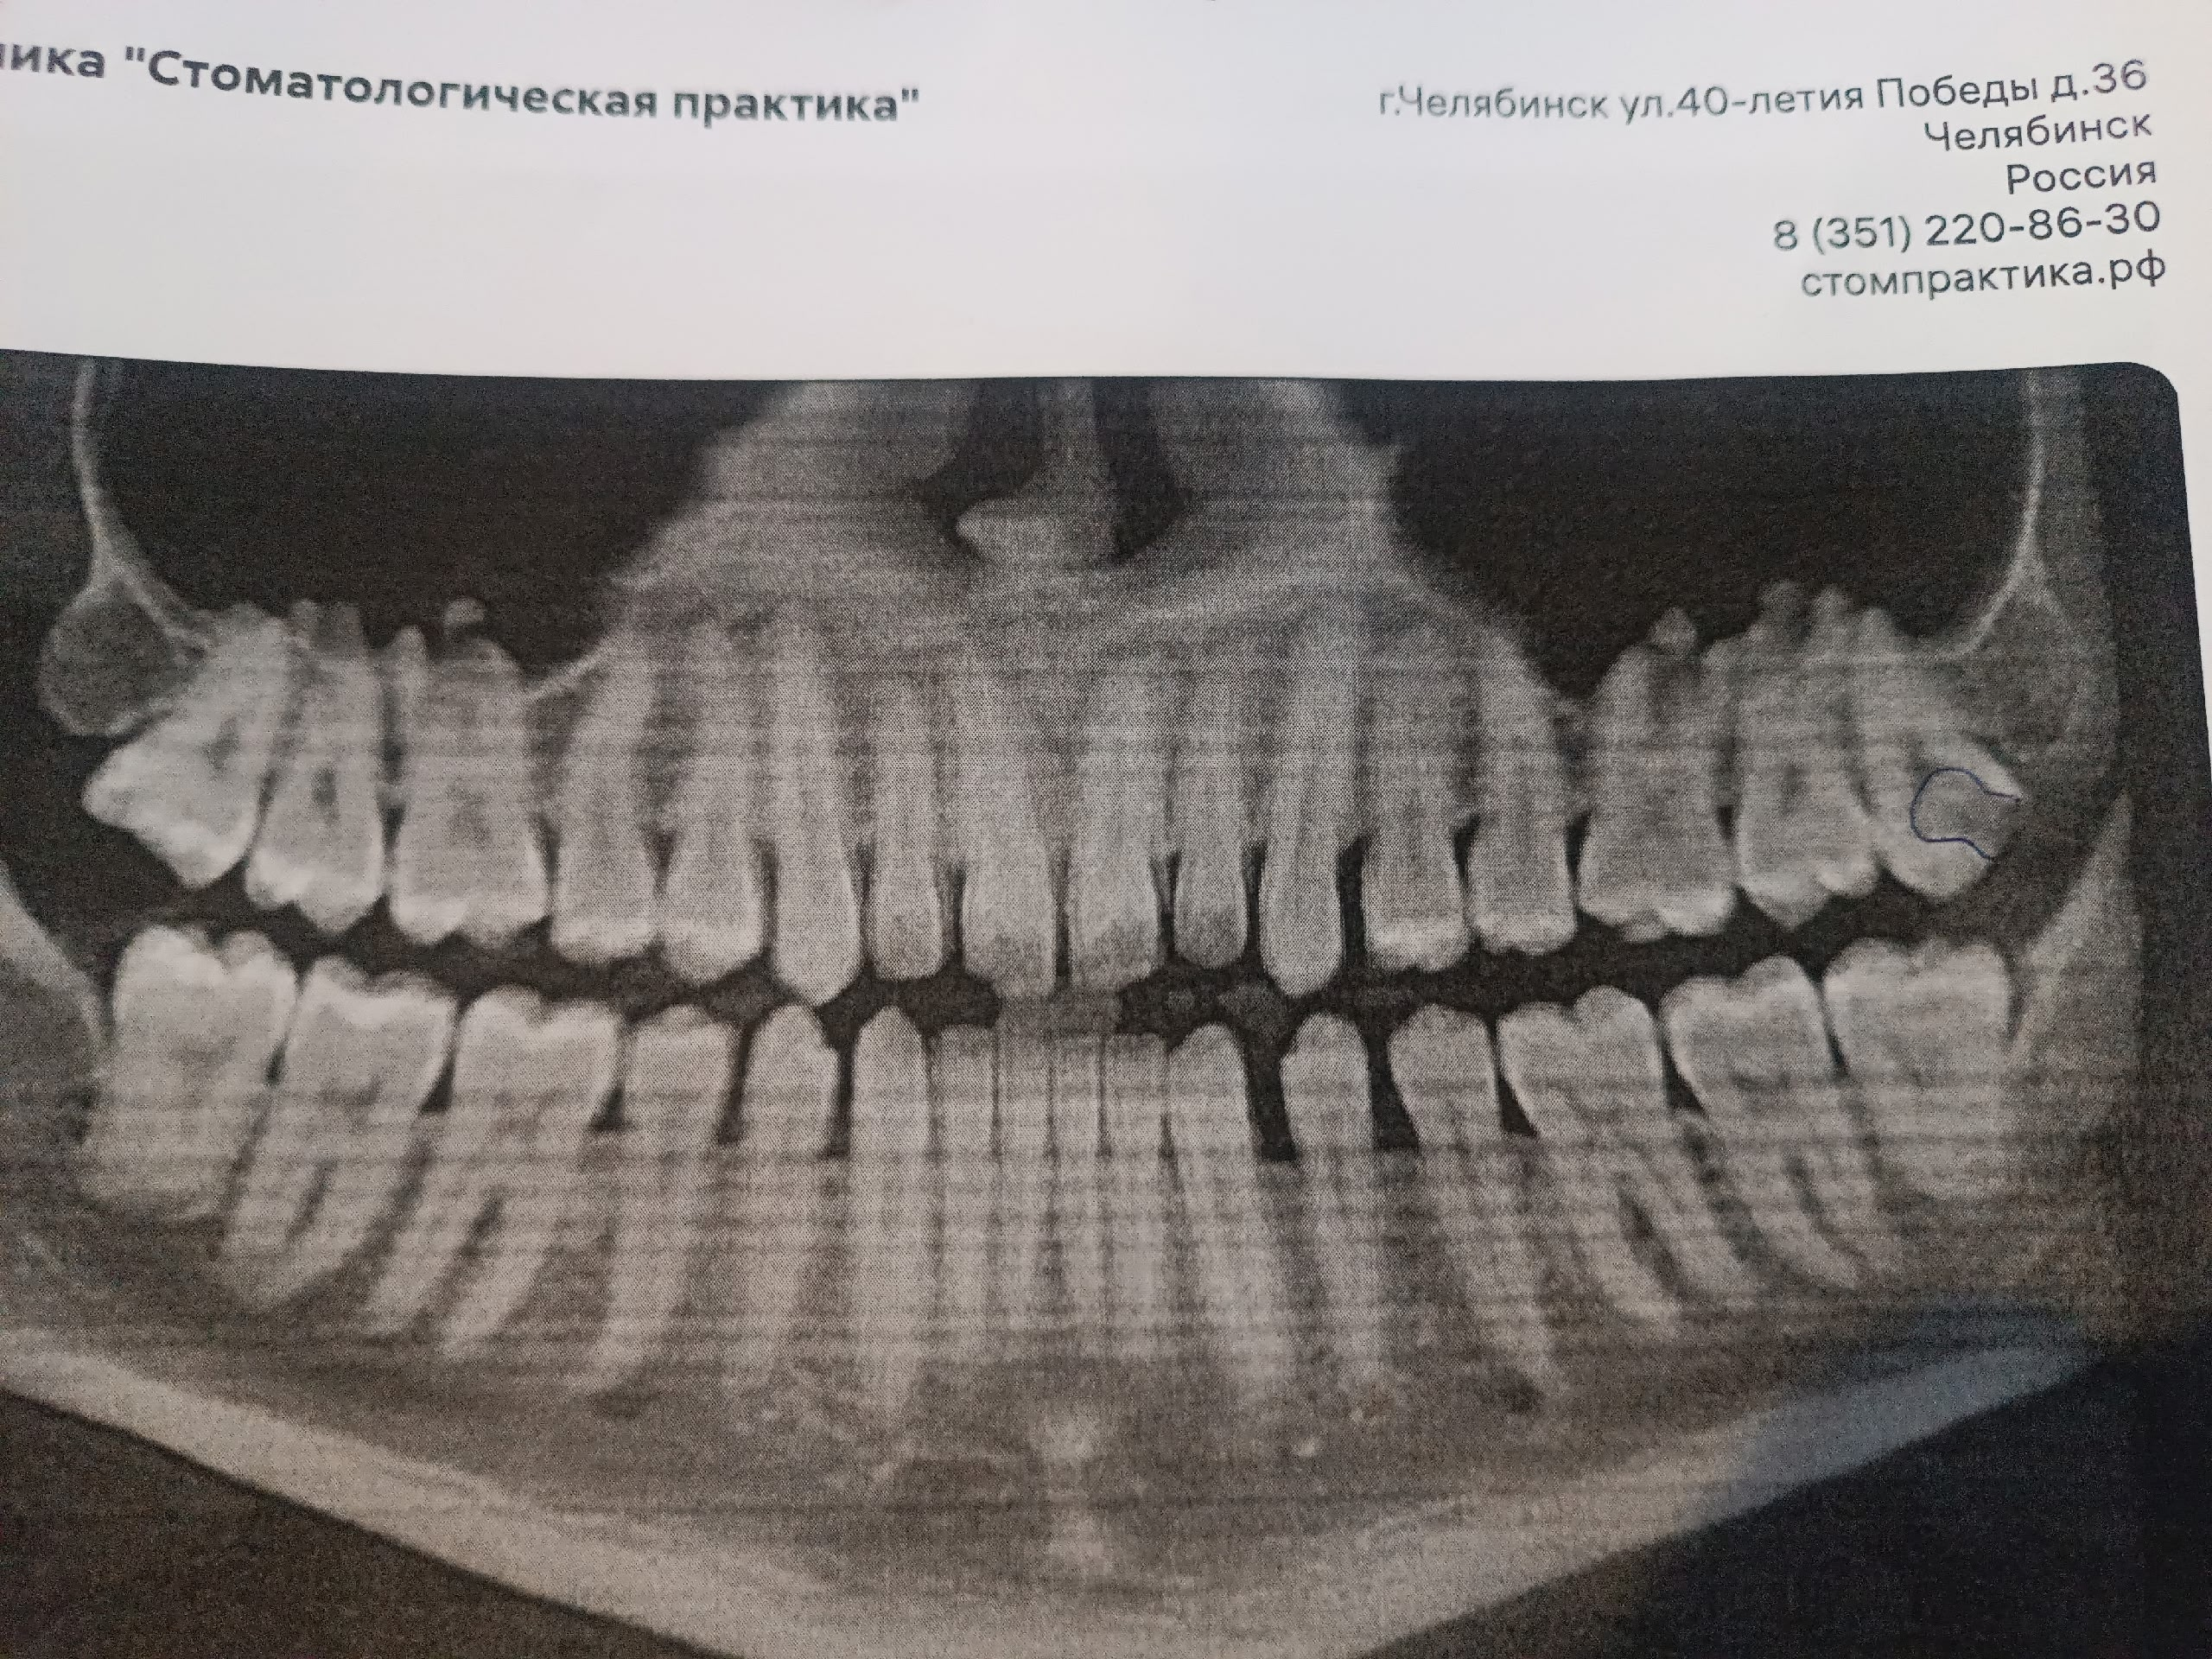

2323.jpg 238Кб, 1412x2047

1412x2047

Аноны, добрый вечер.

Посоветуйте пасту зубную после пломбирования и чистки от камня передних зубов.

Спасибо.

Аноним 06/08/25 Срд 05:38:29 1634925 25

Ска, весь рот в гное, будто бы стоматит, сходил к зубным феям - сказали все збс с корнями зубов и ни одного намёка на кариес где-либо, хотя начиналось всё будто бы флюс и самый пиздец около одного зуба, прописали онли антибиотики, но самое очко , что болезненность ещё и в области мягких тканей подбородка, который и отдает в этот самый пиздец при надавливании - даже будто бы второй подбородок чуть-чуть присутствует, температура и общая слабость, есть риск флегмоны? пиздец за шо(

Аноним 06/08/25 Срд 10:08:53 1634947 26

Как профиль лица меняется после удаления восьмерок? В инете нашел только фотки до/после у женщин, и вроде как челюга уменьшается. У мужиков так же? После удаления не получится больше моггать челюхой омежек?

Аноним 07/08/25 Чтв 13:36:06 1635134 27

>>1634947

>Как профиль лица меняется после удаления восьмерок